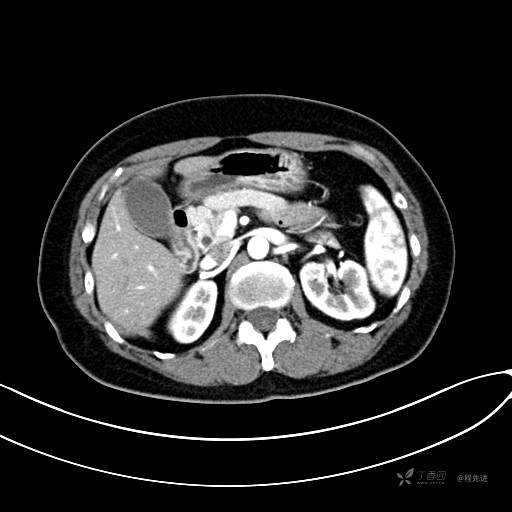

CT增强门脉期